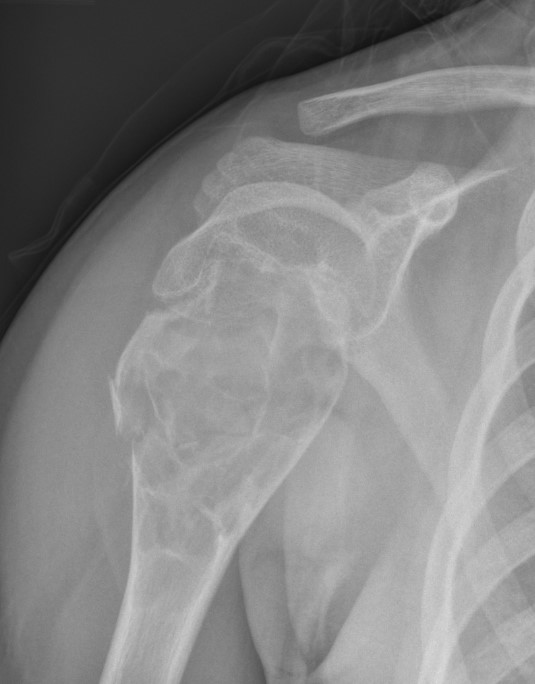

Site

Metaphysis of long bones

- proximal humerus

- femur

- tibia